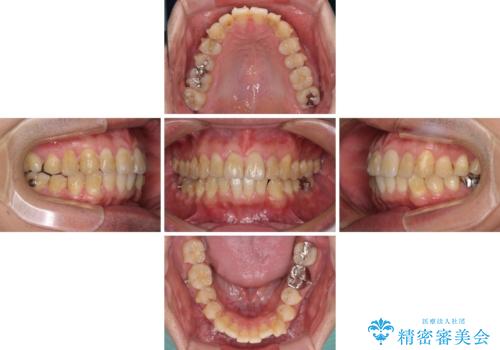

- 前歯のデコボコや八重歯を気にして来院された患者様です。

インビザラインを用いて、歯列を整えることとしました。